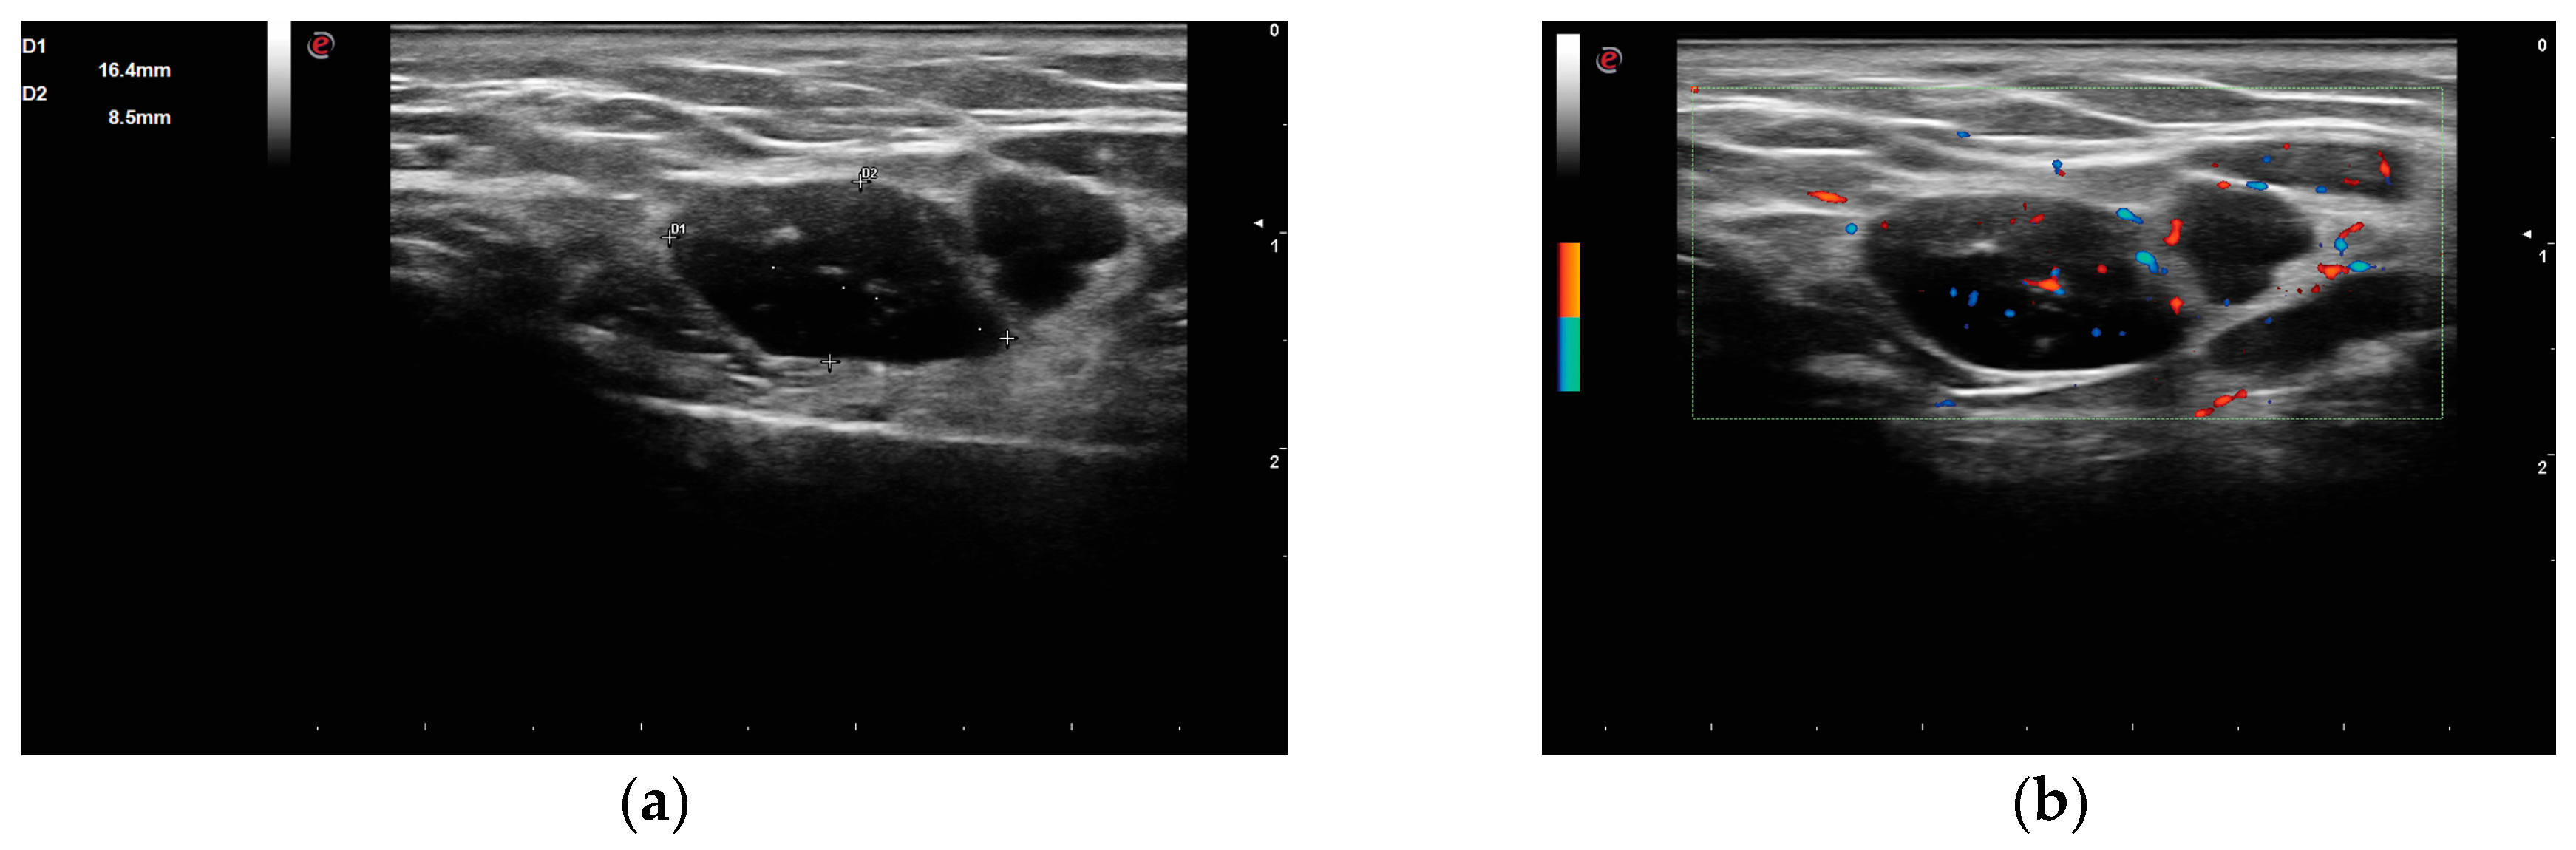

On grey-scale US images, the structure of the glandular parenchyma was greatly altered. Both PGs displayed intense hypo/anechoic areas, some exceeding 6 mm in diameter (Figure 3a). These structural changes were distributed to a significant extent throughout both PGs, having a near total involvement. Homogenous areas of residual glandular tissue were scarcely observed. Based on the Salaffi et al. scoring system [4], a grade 4 PIH was established. In Doppler mode, increased vascularity was observed in the residual tissue (Figure 3b), scoring 2 on a semi-quantitative scale [5].

Figure 3.

US (ultrasound) image of PGs, longitudinal section. (a) left PG displays severe structural changes, multiple large and well-defined, almost anechoic areas, with a maximum diameter of 16 mm; (b) power Doppler of left PG shows a moderate vascularization index, with spots inside the hypoechoic areas and along the residual glandular tissue surrounding the cysts.